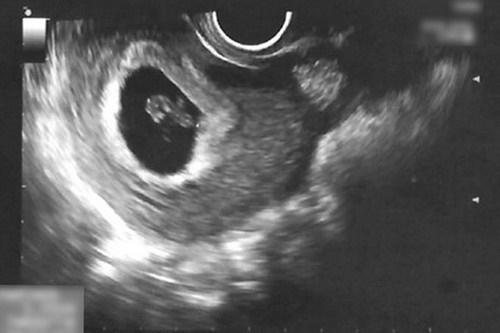

左圖:陳女士懷孕第六週,透過超音波檢查發現子宮腔內出現血塊(紅圈處)。

右圖:經過一週的中醫住院治療,子宮腔內血塊已消失,且胎兒順利成長。